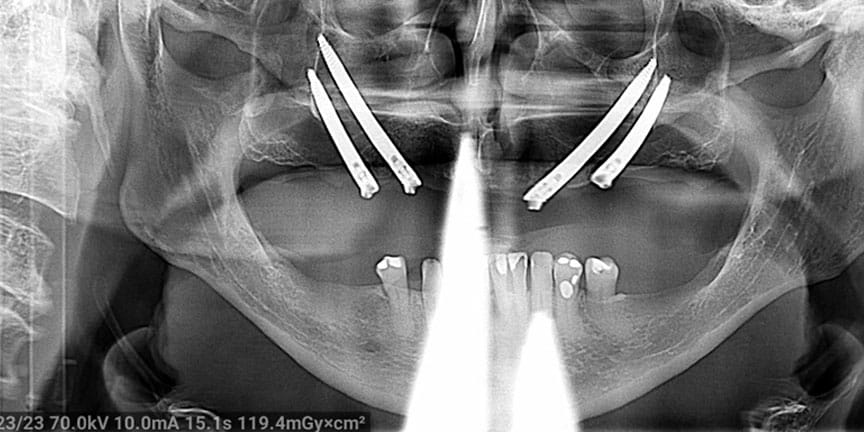

Difficult Cases

We treat patients when other providers cannot manage. CLICK HERE